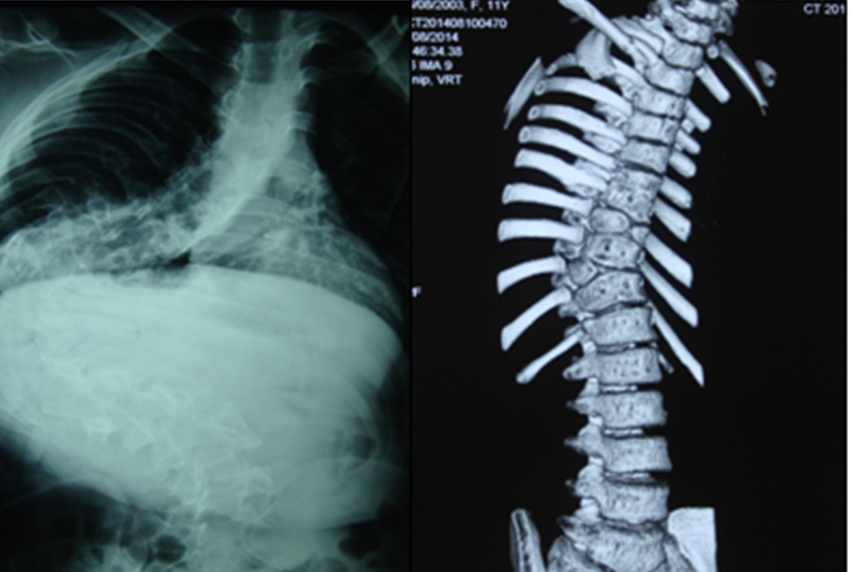

大家看个胸椎侧弯.

胸椎压缩性骨折

常见脊柱疾病的x线分析ppt